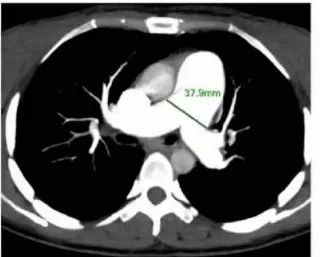

2.肺动脉CT血管造影技术(CTPA)

图 肺动脉高压患者CTPA影片